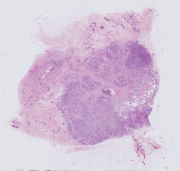

左卵巢旁子宫阔韧带 |

女, 36岁, 患者女,36岁,因“子宫内膜异位症术后一年”,复发5个月入院... |